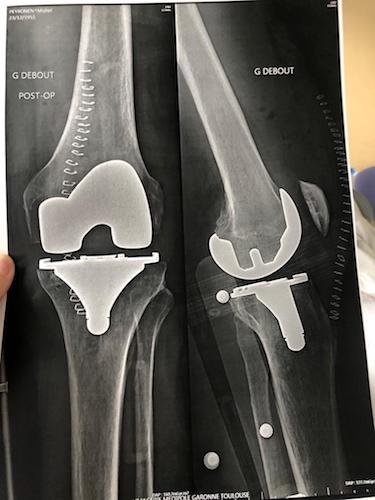

Rassurez-vous, son genou tout neuf en titane à tenu ; mais je ne vous dis pas l’état du pare choc de l’auto !

Le genou de Michel

(voir aussi ici : viewtopic.php?t=542 )